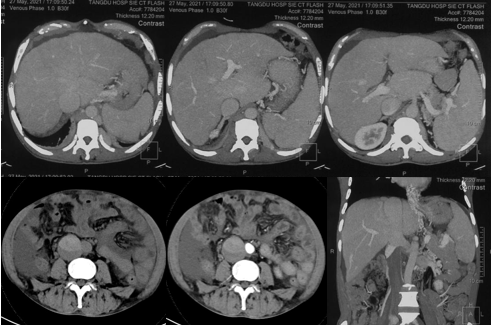

6月20日,患者及家屬懷揣著忐忑的心情來到西安國際醫(yī)學中心醫(yī)院找到韓國宏教授,韓教授詢問病情后閱患者外院CT片,明確診斷布加綜合征,同時發(fā)現了一個新的問題,在詢問病史時了解到患者近一周雙下肢乏力伴腫脹明顯加重,遂立即安排了急診CT,證實下腔靜脈內急性血栓形成!

6月22日,在韓國宏教授的帶領下,患者于消化介入診療中心行下腔靜脈開通術。術中可見:下腔靜脈全段擴張,膜性閉塞,腎靜脈平面以下可見血栓形成并伴有粗大的側枝靜脈,遂對狹窄段球囊擴張并植入支架,術后下腔靜脈血流通暢,側枝消失。術后第2天,患者腹壁靜脈曲張幾乎消失不見,走路也輕快了許多。明明只是薄薄的一層膜,為什么開通起來這么難?韓教授指出,盡管布加綜合征介入開通技術已使創(chuàng)傷降到了最低,但受到患者個體差異及醫(yī)療水平參差不齊的限制,仍有可能出現嚴重的并發(fā)癥,主要包括:心包積血、縱隔血腫、心包填塞甚至下腔靜脈撕裂引起的大出血等。而其發(fā)生率與術者的操作熟練程度及經驗有很大的關系。